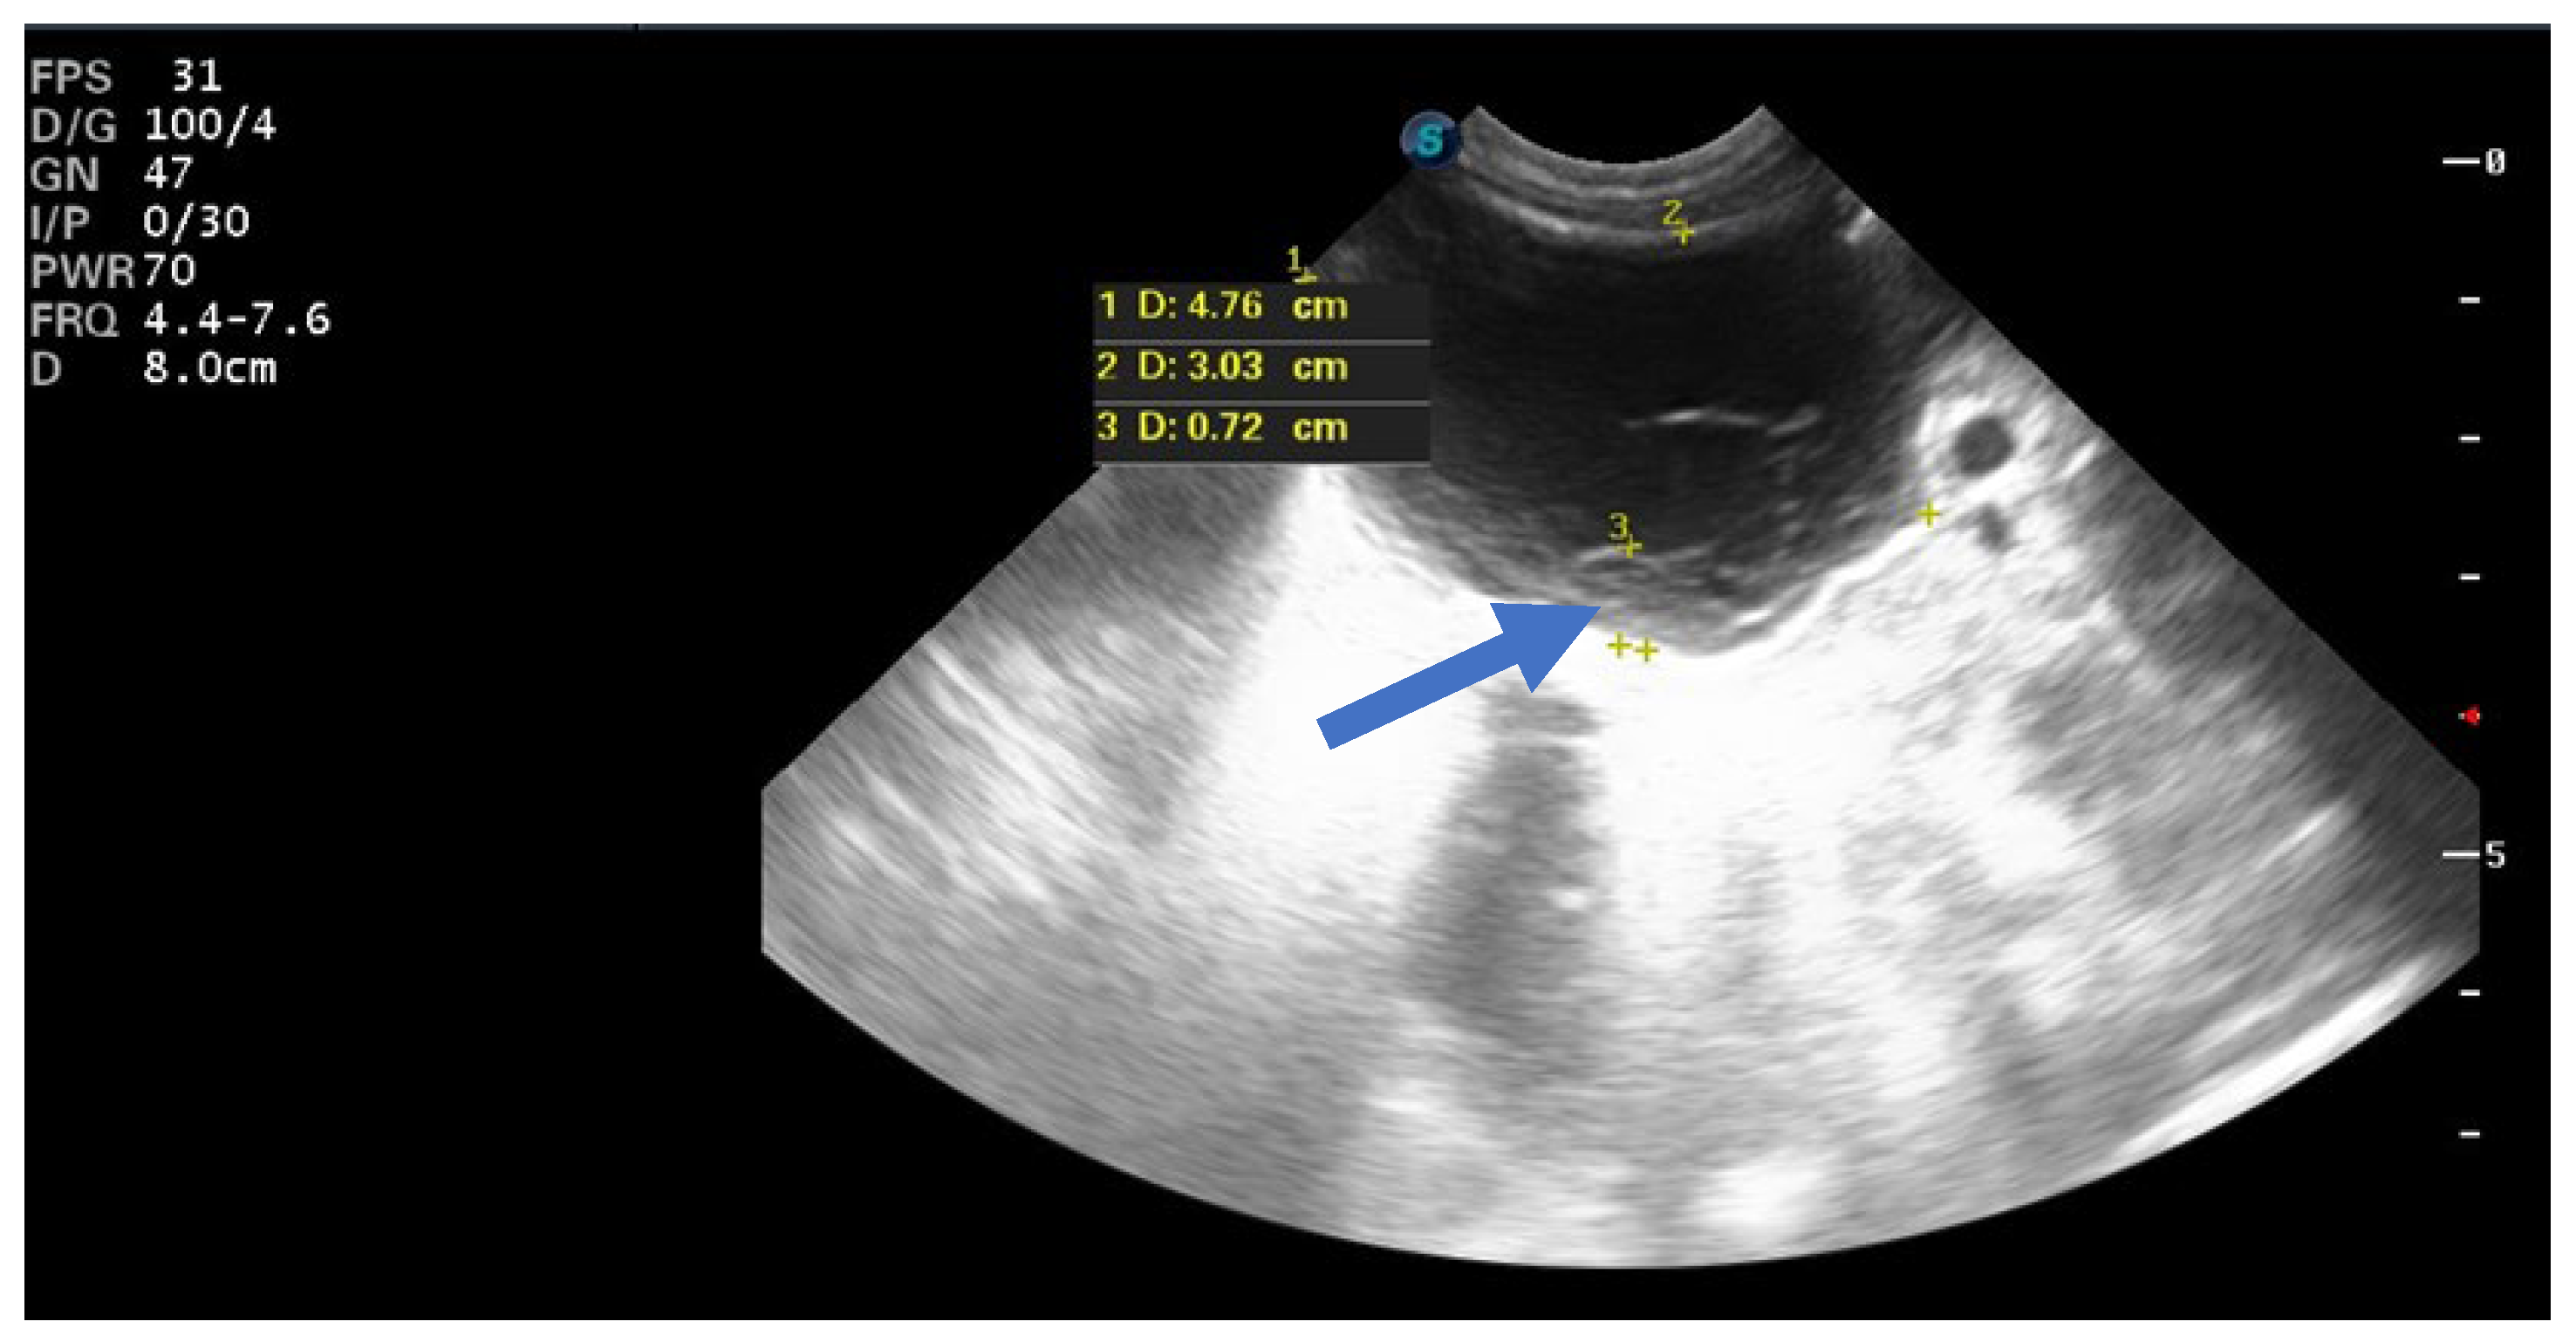

One hemorrhagic-looking cyst remained unchanged after two months but resolved completely after 8 months, and no follow-up evaluation information was available for another case (Figure 7).

Figure 7.

Ultrasound image of a simple cyst showing a blood clot (arrow) that resolved spontaneously after 8 months postpartum.